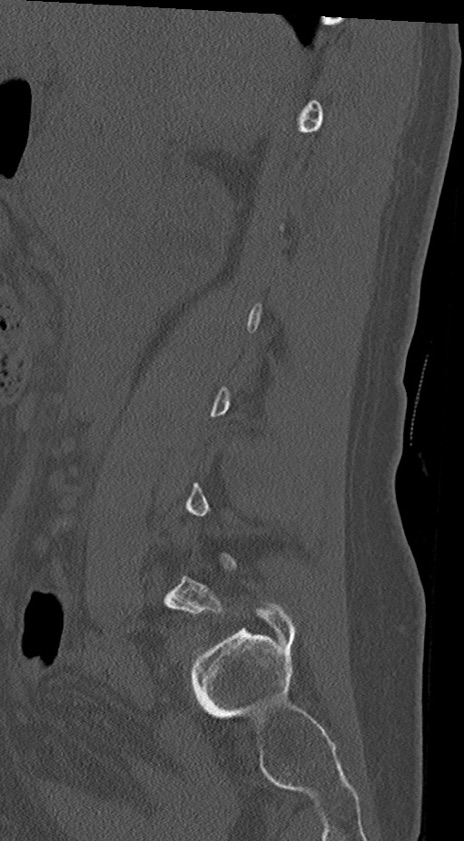

【整形】TIPS症例4 腰椎CT(矢状断像)

腰椎CT

冠状断像